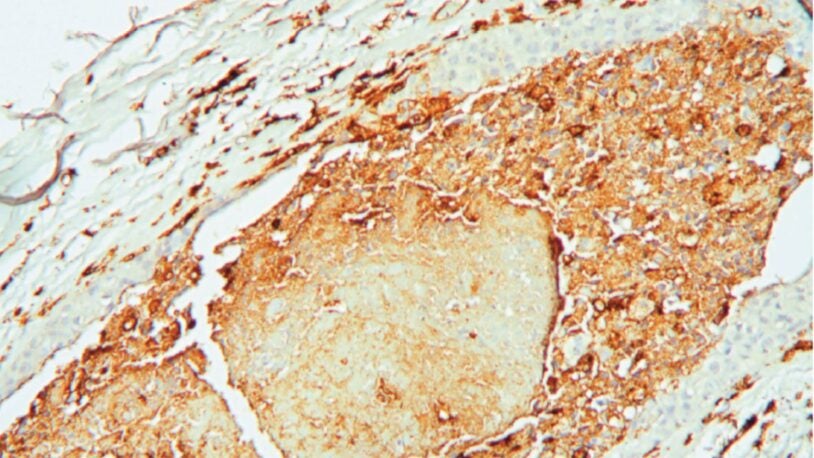

An angry peacock is no joke. Like the colorful bird and its tall tail feathers, cancer biology can make for some eye-catching images. Read the story »

That’s not the Starship Enterprise burning up in space. It’s an up-close look at precancerous pancreatic lesions and the mucus they produce. Read the story »